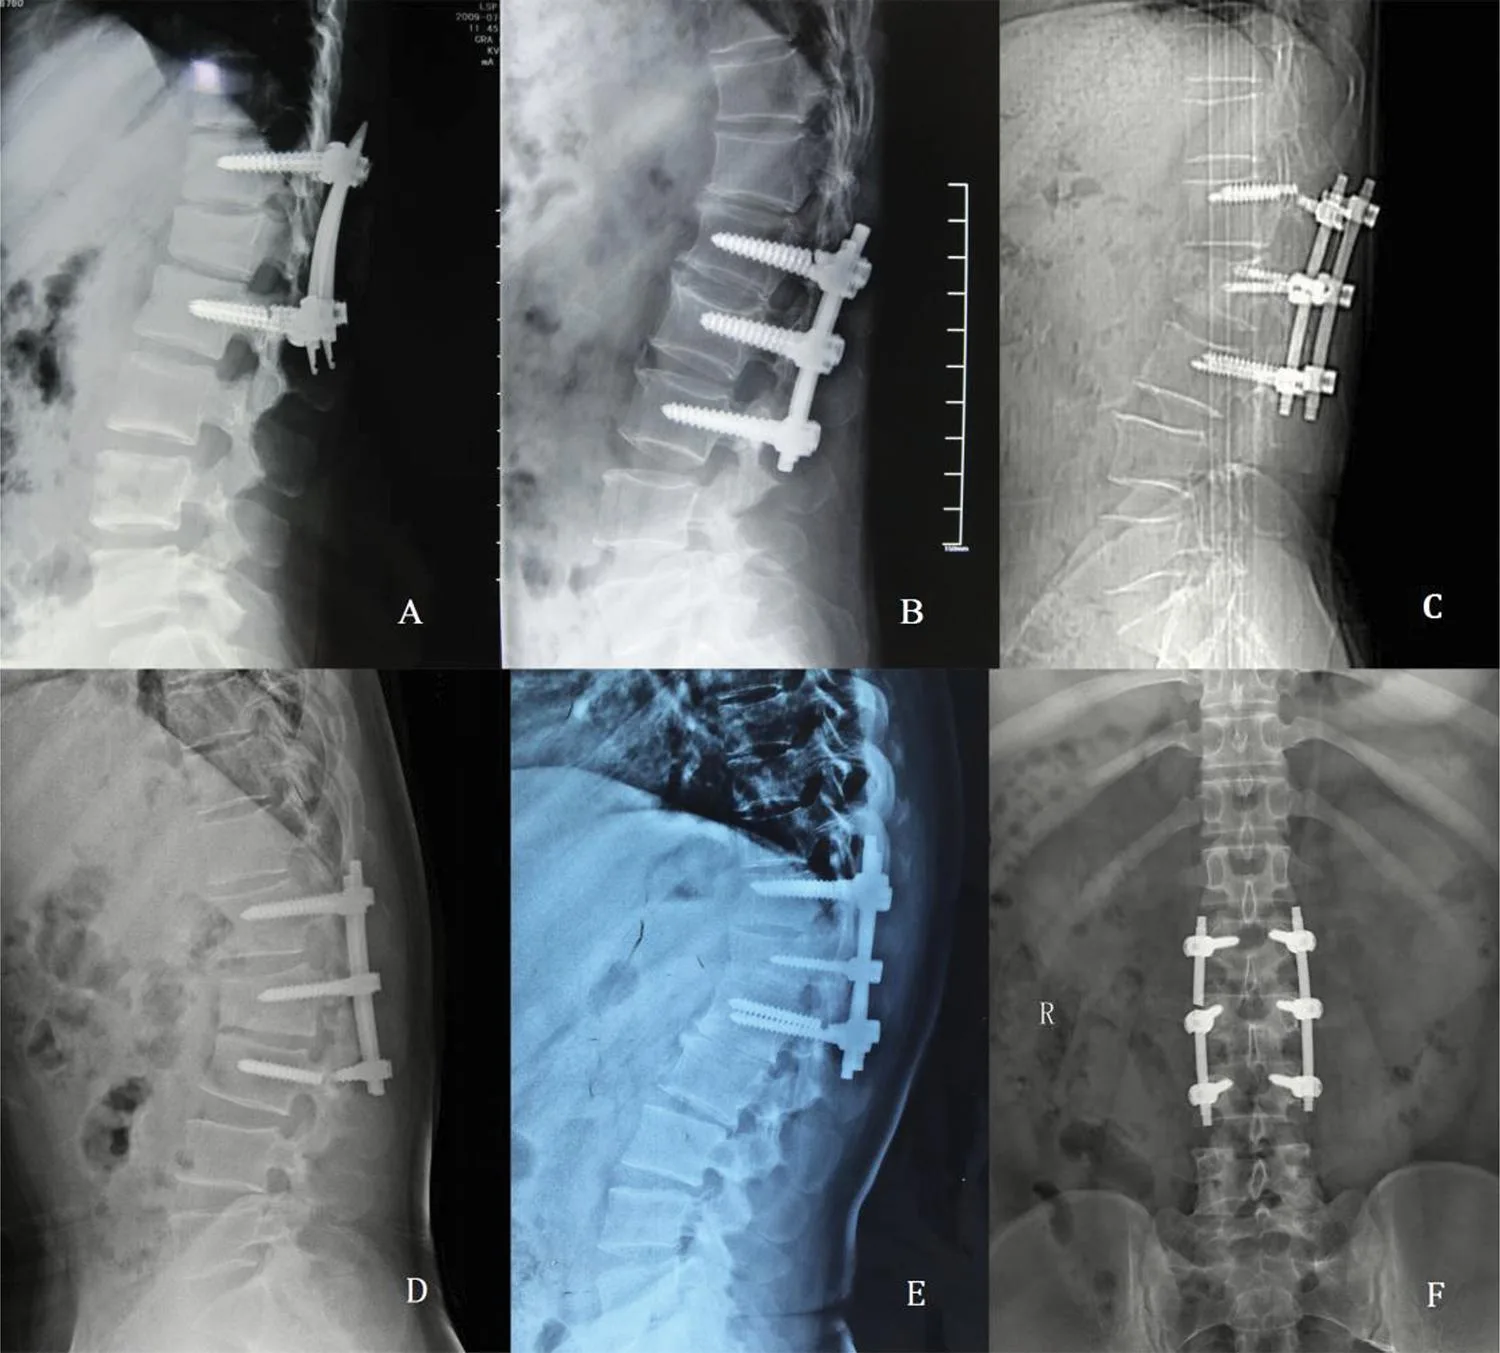

Better Radiopacity

Imaging scans like X-rays and CT scans can see through the HA covering better because it is less radioactive. Better radiopacity lets doctors see more clearly where the screws are and how well they’re integrating into the bone. This leads to better planning for surgery and better review afterward.

The low profile and practical design of HA Coated Poly Axial Screws make them suitable for a number of spinal conditions, such as degenerative disc disease, deformities like scoliosis, kyphosis, lordosis, and injuries to the spine. Because they are polyaxial, they can better adapt to the natural curve of the spine, which lowers the chance of problems and improves patient results.

Orthopedic devices called Break Thru Poly Axial Screws are made to be used in spine operations.

The polyaxial form of these screws gives you more options for where to put them and how to line them up compared to standard monoaxial screws. The “break-thru” design means that the screw head can separate from the shaft, which makes it easier to remove if needed.